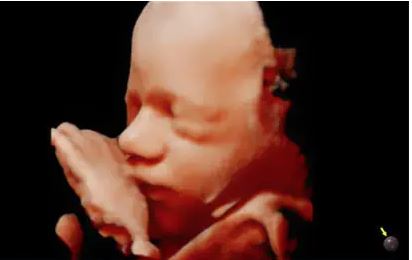

Modes d’imagerie: noir et blanc, doppler couleur, 3D/4D

Technologies d’imagerie redéfinies, optimisées par Crystal Architecture™: Crystal Architecture™ est une architecture d’imagerie qui combine CrystalBeam™ et CrystalLive™ tout en s’appuyant sur S-Vue Transducer™, pour fournir des images d’une clarté cristalline.

– CrystalLive™ est le moteur d’imagerie échographique Samsung le plus récent, avec un traitement d’image 2D, un rendu 3D et un traitement du signal couleur améliorés, dans lequel on obtient des performances d’image enrichies et un flux de travail efficace pendant les cas complexes.